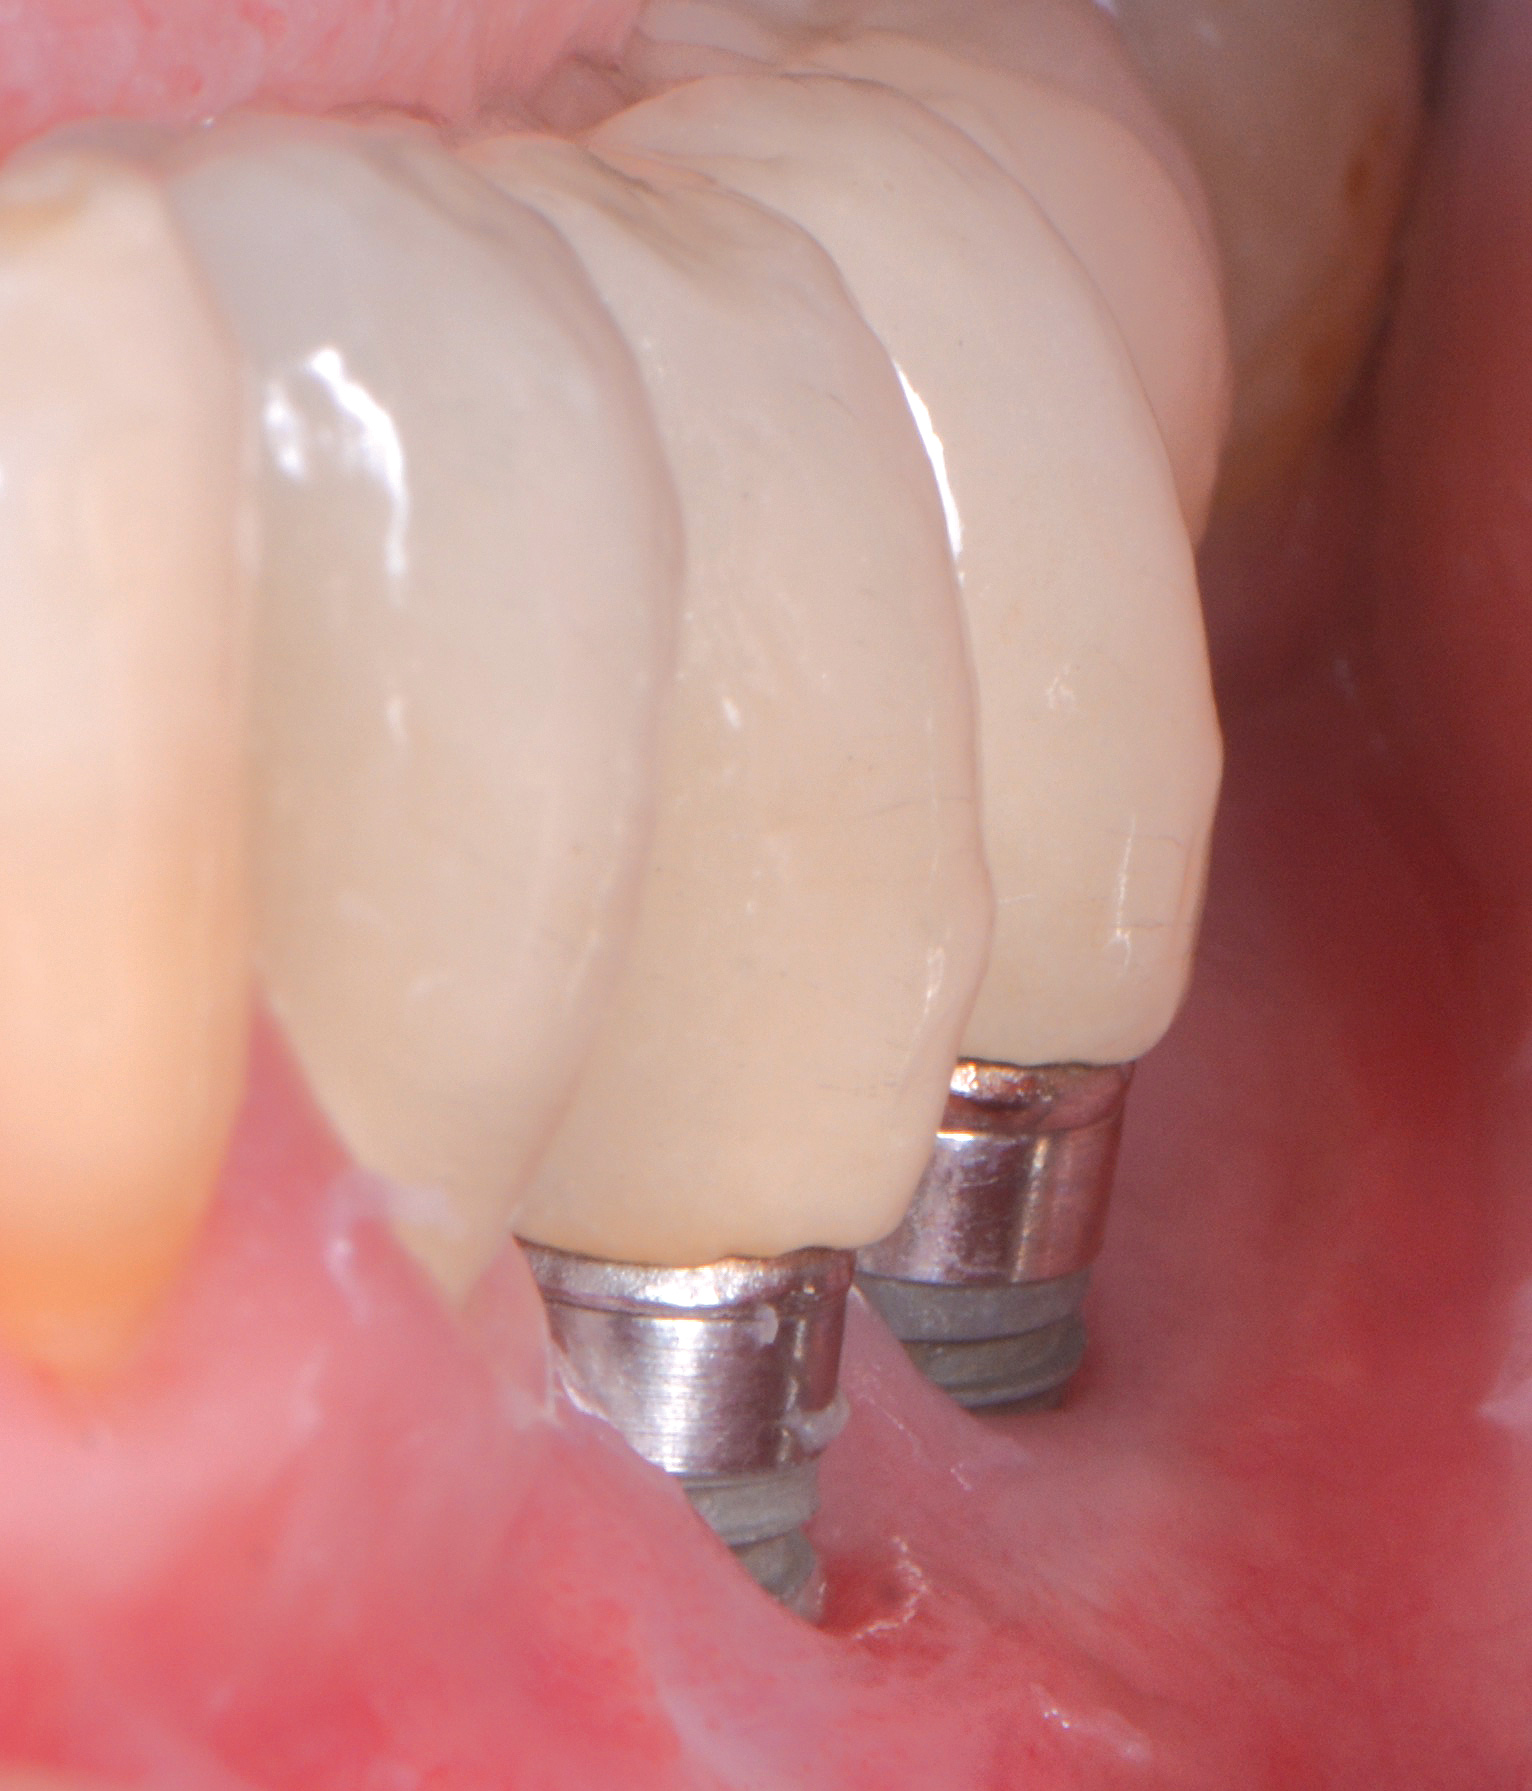

Fig 5. Clinical view of implants depicting suggested bone loss. Plaque was present throughout, and the distal-most implant had substantial purulent exudate.

Figure 5

Fig 6. From a more anterior view, it was apparent that the labial positioning of these implants was outside the alveolar housing.

Figure 6

Fig 7. Radiographic image of the area suggesting severe bone loss around the dental implants.

Figure 7

Studies have demonstrated that much like teeth, dental implants have a certain biologic dimension established following their healing after surgery and much of this understanding comes from evidence obtained from animal studies.18,19 However, in a seminal article on implant placement, Salama et al20 further highlighted the concept of bone surrounding an implant. A violation to the dimension of bone present in any of the buccal-palatal, mesial-distal, or apical-coronal directions will lead to bone loss (Figure 5 through Figure 7). This relates to the blood supply necessary to maintain the bone surrounding a dental implant. If an implant is placed in a position in which the minimal bone dimensions are not respected, crestal loss can be anticipated. While this may represent a contained lesion and remain static, it may not always be the case. In implants designed with a surface roughened to the top, suboptimal plaque control can lead to ongoing bone loss, because the exposed roughened surface is challenging to clean and will act as a plaque-retentive feature.21